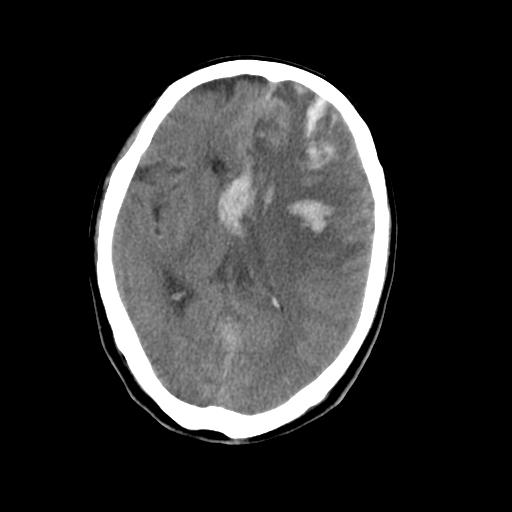

男,78岁。自诉两周前因右侧肢体障碍行ct检查,诊断为脑梗塞(患者ct片已丢失)治疗好转后出院。现因意不清12小时,又行ct检查。

结合病史考虑左侧额颞顶叶出血性脑梗塞。

结合病史考虑左侧额颞顶叶出血性脑梗塞